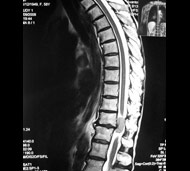

Спинальна магнітно-резонансна томографія (МРТ). Замість радіаційного випромінювання в МРТ використовуються потужні магнітні і радіохвилі для отримання зображення поперечного перерізу хребта. МРТ чітко відображає спинний мозок і нерви і забезпечує краще зображення пухлин кісток, ніж комп'ютерна томографія (КТ). Вам можуть ввести в вену кисті або передпліччя контрастну речовину, яка висвітлює деякі пухлини. Крім цього, використовують сканери з високою інтенсивністю сигналу для виявлення невеликих пухлин, які можна не помітити.